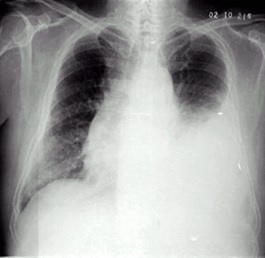

02卷-5.女性,55歲,胸悶、氣短5天,加重1天。診斷(本題滿分2.00分)

A.右上肺炎

B.左側(cè)胸腔積液

C.左下肺不張

D.左肺癌

本題答案:B

題目解析:【該題針對(duì)“X線-胸腔積液”知識(shí)點(diǎn)進(jìn)行考核】